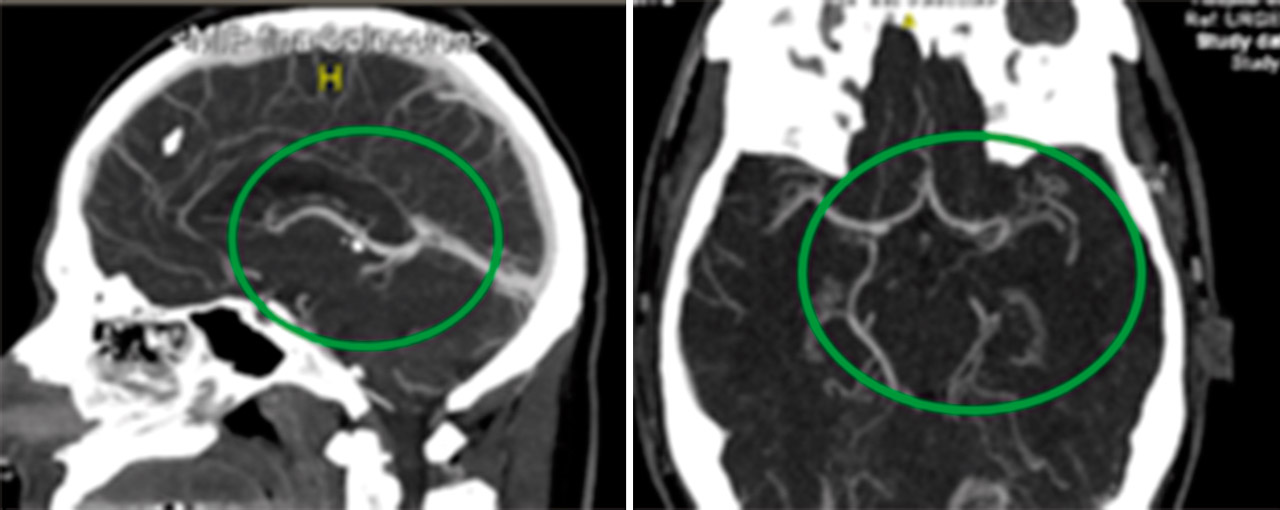

Se procedió a la desintubación, objetivando agitación y alteración para la emisión y comprensión del lenguaje. Ante la sospecha de un accidente cerebrovascular se realizó una tomografía computarizada (TC) craneal multimodal objetivando un aumento en los tiempos de tránsito medio, tiempo pico y del flujo sanguíneo, sin alteraciones en el volumen cerebral, compatibles con área de penumbra isquémica del 100%. En angio-TC, se evidenció un defecto de repleción en la arteria cerebral media izquierda, segmento M1, de 12,5 mm (Figura 6). Ante estos hallazgos, se inició el tratamiento trombolítico, 2 horas después de verle asintomático por última vez. A pesar de la mejoría progresiva, se decidió realizar una arteriografía para valorar la extensión del defecto, viendo una imagen arteriográfica compatible con oclusión crónica de M1 izquierda, sustituida por múltiples colaterales, dando el aspecto de Moyamoya (Figura 7).

Ingresó en la Unidad de Ictus 5 horas después, donde se efectuaron estudios diagnósticos. En una nueva TC multimodal persistía el defecto de repleción de M1 izquierda y múltiples vasos colaterales; diagnosticándose de síndrome de pseudo-Moyamoya.

En las pruebas de imagen realizadas, se halló obstrucción crónica en la arteria cerebral media con aumento de la circulación colateral para suplir el defecto, simulando un síndrome Moyamoya, una vasculopatía de etiología desconocida que presenta oclusión progresiva de la porción proximal de arterias cerebrales, desarrollándose vasos colaterales compensatorios(4). Dicha patología no precisa tratamiento en situación asintomática pero es necesario, en este contexto u otros, prevenir situaciones que puedan producir hipoperfusión cerebral.